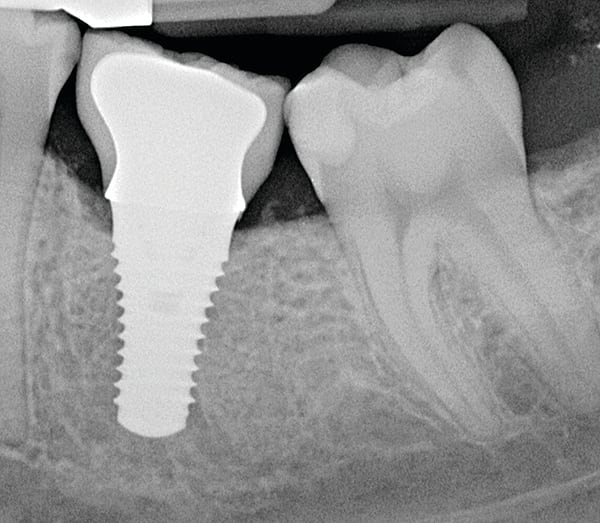

Given what is known about the etiology of peri-implant mucositis and peri-implantitis and the importance of rendering treatment at the earliest possible stage, there are steps that clinicians should take to prevent and minimize the negative sequelae of these biologic complications. Peri-implant diseases present in two forms: peri-implant mucositis (Figure 1 and Figure 2) and peri-implantitis (Figure 3 and Figure 4). Both involve an inflammatory reaction in the tissues surrounding an implant—ie, BOP and/or suppuration and probing depths usually exceeding 4 mm.1,2 However, when there is also bone loss present beyond the physiologic remodeling that may occur after implant placement, a diagnosis of peri-implantitis should be made because this condition, when compared to mucositis, is far more serious and difficult to resolve.3

The authors, both of whom are periodontists, believe that dentists should make every effort to save a failing tooth before replacing it with an implant because implants are not immune to complications and do not integrate 100% of the time. Moreover, the authors consider efforts to save implants far preferable to extraction and replacement with another implant given the time and the cost for such treatment. They, along with their colleagues, have successfully achieved improvement in bone loss for both teeth28 and implants with a regenerative approach that emphasizes surface decontamination. Dental implants, with their roughened surface topography that is designed to enhance osseointegration, require that this comprehensive regenerative approach employ these tactics: aggressive surface decontamination with mechanical and chemotherapeutic approaches; the administration of systemic antibiotics; regenerative therapy with bone and bone replacement grafting; and the use of biologics and barrier membranes, all followed by a tightly controlled maintenance approach (Figure 8 through Figure 11). In fact, in one case series article this approach to care has demonstrated promising results for up to 8.5 years postsurgery.29,30 This therapy is quite complex and significant experience is essential if success is to be consistently achieved.